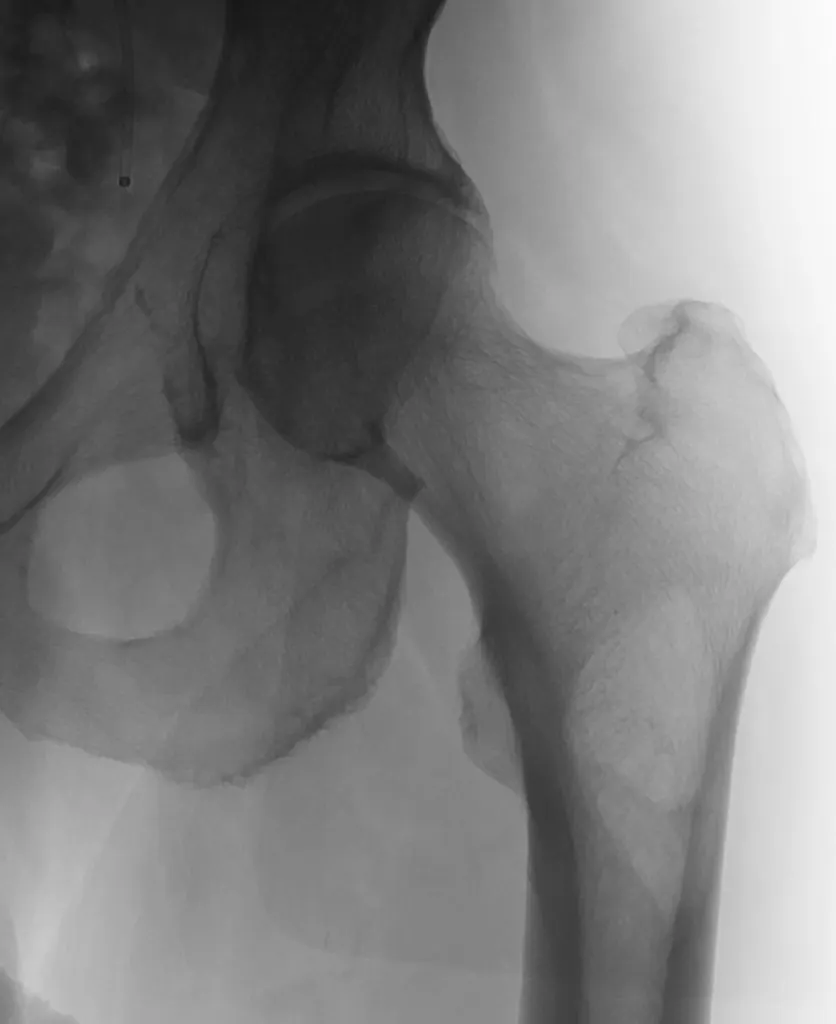

65 year old with a left femoral renal metastasis lesion. Angiograms showing vascularity of the lesion. The two annotated images show the tortuosity of the vessel supplying the lesion. The dotted orange coloured line shows the path of the vessel. It was not possible to cannulate this artery with conventional microcatheters.